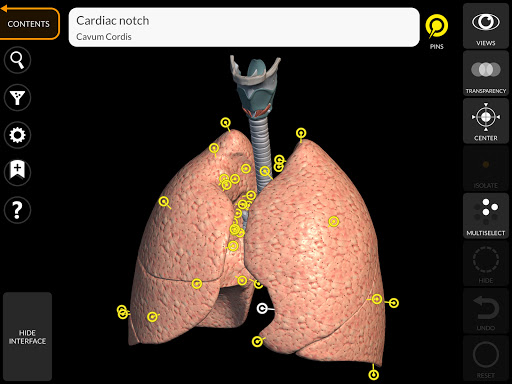

يتيح لك "Anatomy 3D Atlas" دراسة التشريح البشري بطريقة سهلة وتفاعلية.

من خلال واجهة بسيطة وبديهية، من الممكن ملاحظة كل بنية تشريحية من أي زاوية.

تتميز النماذج التشريحية ثلاثية الأبعاد بتفاصيل خاصة ودقة تصل إلى 4K.

يسهل التقسيم حسب المناطق والمناظر المحددة مسبقًا مراقبة ودراسة الأجزاء الفردية أو مجموعات الأنظمة والعلاقات بين الأعضاء المختلفة.

• الجهاز التنفسي

• من خلال تحديد نموذج أو دبوس، يظهر المصطلح التشريحي ذي الصلة

• يمكن عرض المصطلحات التشريحية بلغتين في وقت واحد